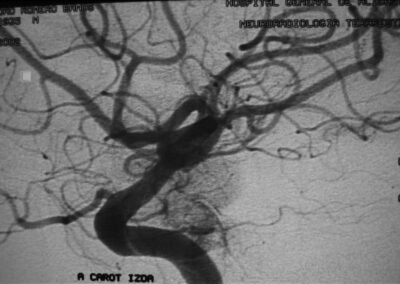

El diagnóstico se puede confirmar y el tumor localizar mediante:

• Angiografía cerebral